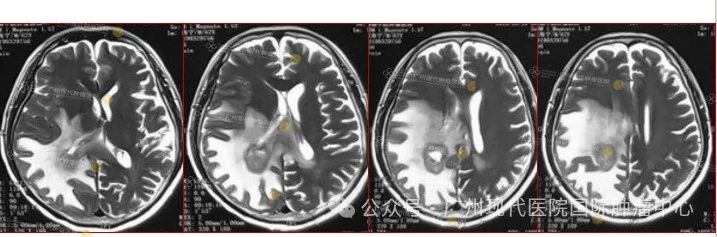

2015-11,头颅MR检查提示颅内转移

2018-11,颅内肿瘤进展,无法接受后续治疗

2019-3,接受脑瘤粒子植入术

2019-7,颅内肿瘤基本消失,正常生活至今

2019年7月,颅内肿瘤已基本消失